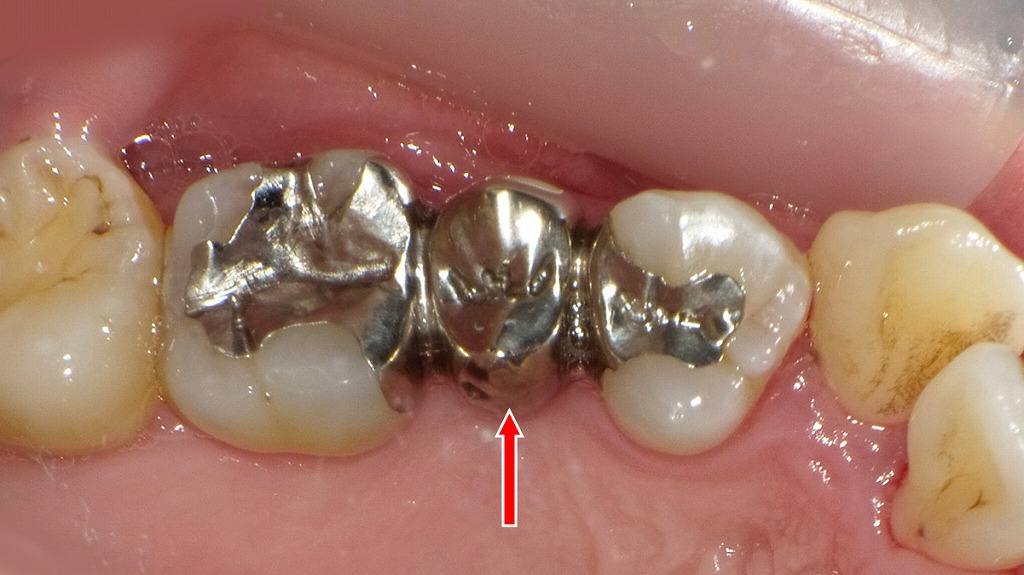

✨同症例咬合面観

内側は金属

接着ブリッジ症例の咬合面から見た所です。見える部分の歯質は削らず、内側のみを削ります。内側に金属が使われていますが、正面から見ると金属は見えない構造になっています。